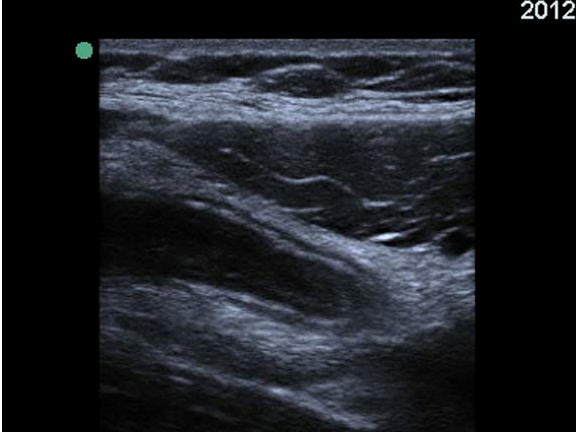

Screen shot 2012-12-23 at 8.58.46 PM